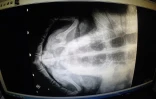

Lundi 21 janvier, la jeune tortue imbriquée nommée Victoria a fait de nombreuses crottes dans son bassin, dont une contenait du fil de pêche. Après analyse, le centre de soins de Kélonia confirme qu'il y avait bien au bout de 1m46 de fil de pêche et l'hameçon observé sur les radios. L'animal est donc maintenant débarrassé de la totalité des cinq hameçons observés lors de son arrivée au Centre de soins de Kelonia il y a 2 semaines. Elle va pouvoir retrouver le bassin pirogue.